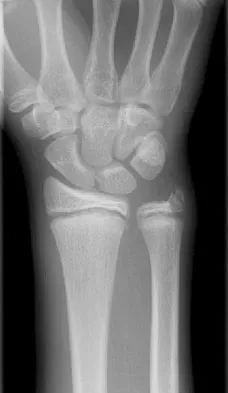

A 14-year-old boy reports progressive right wrist pain. Radiographs are shown in Figure 3a, and a photomicrograph is shown in Figure 3b. What is the most likely diagnosis?

Explanation

The radiographs show a benign-appearing, well-defined lytic lesion with a thin rim of surrounding reactive bone. The photomicrograph shows spindle cells with a myxoid cartilaginous matrix. These findings are diagnostic of chondromyxoid fibroma. This is a rare, benign tumor that usually causes pain and can be locally aggressive. Lersundi A, Mankin HJ, Mourikis A, et al: Chondromyxoid fibroma: A rarely encountered and puzzling tumor. Clin Orthop Relat Res 2005;439:171-175.